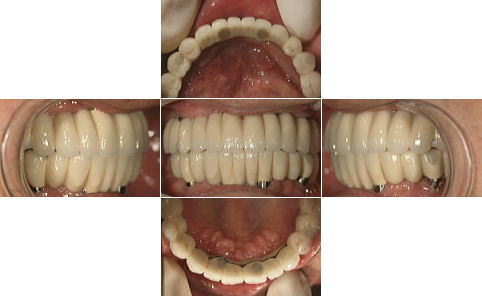

| 上顎、下顎共にグラツキの著しい歯は抜歯し、上顎はAll-on-4、下顎奥歯は通常のインプラントブリッジとしました。 | |